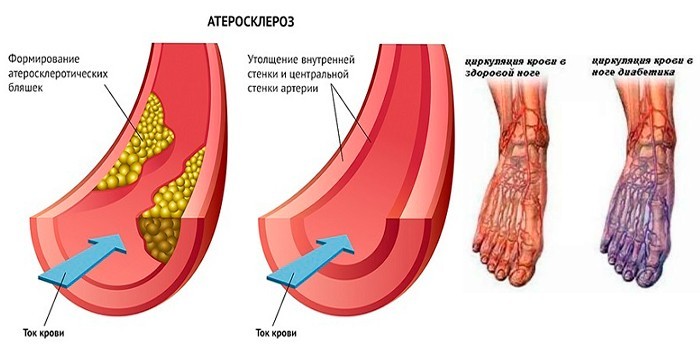

Изображения, связанные с атеросклерозом нижних конечностей и его лечением